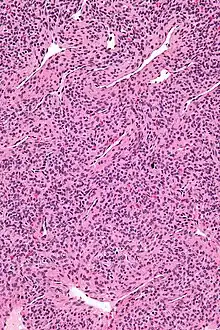

Micrograph of a myopericytoma. H&E stain. | |

Myopericytoma is a rare perivascular soft tissue tumour. It is usually benign and typically in the distal extremities.[1]